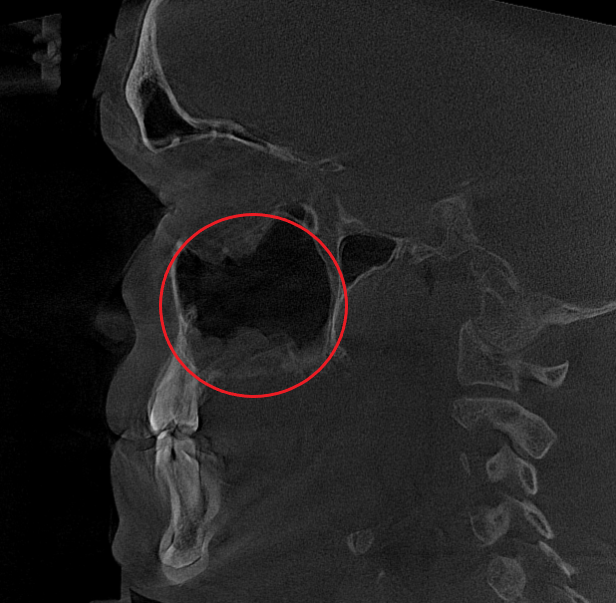

- Компьютерная томография (КЛКТ) околоносовых пазух и височных костей: Этот высокоинформативный метод диагностики объективно показал искривление носовой перегородки вправо, субтотальное снижение пневматизации (воздушности) левой верхнечелюстной пазухи, что свидетельствовало о хроническом воспалительном процессе. Костно-деструктивных изменений не выявлено.

- Хронический левосторонний верхнечелюстной синусит (J32.0). Длительное воспаление слизистой оболочки левой гайморовой пазухи, подтвержденное КТ.

Послеоперационный период протекал гладко. Проводились регулярные туалеты полости носа, промывание оперированной пазухи, назначались средства для увлажнения и регенерации слизистой оболочки, а также местная антибактериальная терапия. По результатам оперативного лечения носовое дыхание было полностью восстановлено, признаки активного воспаления купированы. Спустя 1.5 месяца после проведенного оперативного лечения проведено КТ околоносовых пазух в динамике, что отражает промежуточный результат оперативного лечения. На снимках: Перегородка носа располагается по центру, оперативно созданное соустье левой верхнечелюстной пазухи функционирует, пневматизация левой верхнечелюстной пазухи значительно улучшилась. Окончательный результат можно будет оценить через 3 месяца после проведенной операции, и при полной пневматизации левой верхнечелюстной пазухи пациент сможет приступить к установке зубных имплантов в верхнюю челюсть слева.